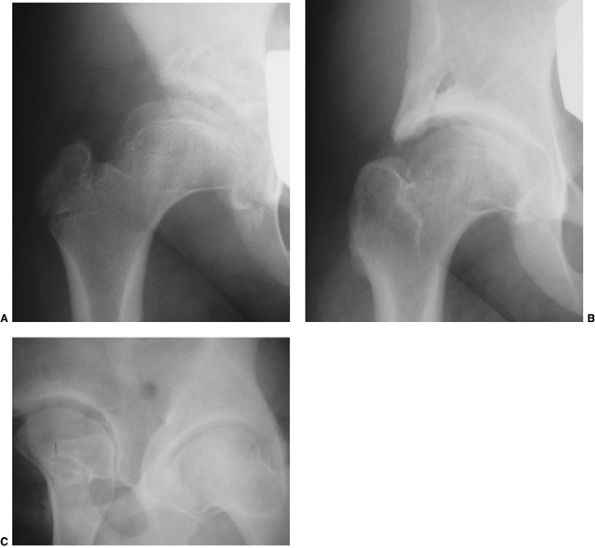

![]() |

Figure 24.28 A 5-month-old child with left developmental dislocation of the hip. A:

Anteroposterior view of the pelvis at diagnosis. The acetabular index is increased, the medial floor of the acetabulum is widened, and the acetabular teardrop figure is absent. There is a well-developed secondary acetabulum, the Shenton line is disrupted, and the femoral ossific nucleus is decreased in size. The femoral head is located in the upper outer quadrant, as defined by Hilgenreiner and Perkins lines. B: Anteroposterior view of the pelvis with a hip Pavlik harness in place to demonstrate an excellent reduction. Note the hyperflexed position. C: Anteroposterior view of the pelvis at 9 months of age shows reduction, early appearance of the teardrop figure, and improvement in the acetabular index. D: Anteroposterior view of the pelvis at 31 months of age. There is marked improvement in the acetabular teardrop figure and acetabular development. E: Anteroposterior view of the pelvis at 5 years of age. There has been continued improvement in acetabular and femoral head development. |

Figure 24.29 A 6-month-old girl with apparent left hip subluxation and acetabular dysplasia secondary to excessive anteversion. A:

Diagnostic anteroposterior view of the pelvis. Note the increased acetabular index, the poorly developed teardrop figure, and the small ossific nucleus. B: Anteroposterior view of the pelvis in the fixed abduction brace. Excellent reduction of the hip has been achieved. C: Anteroposterior view of the same patient at 5 years of age. The left hip appears normal. |